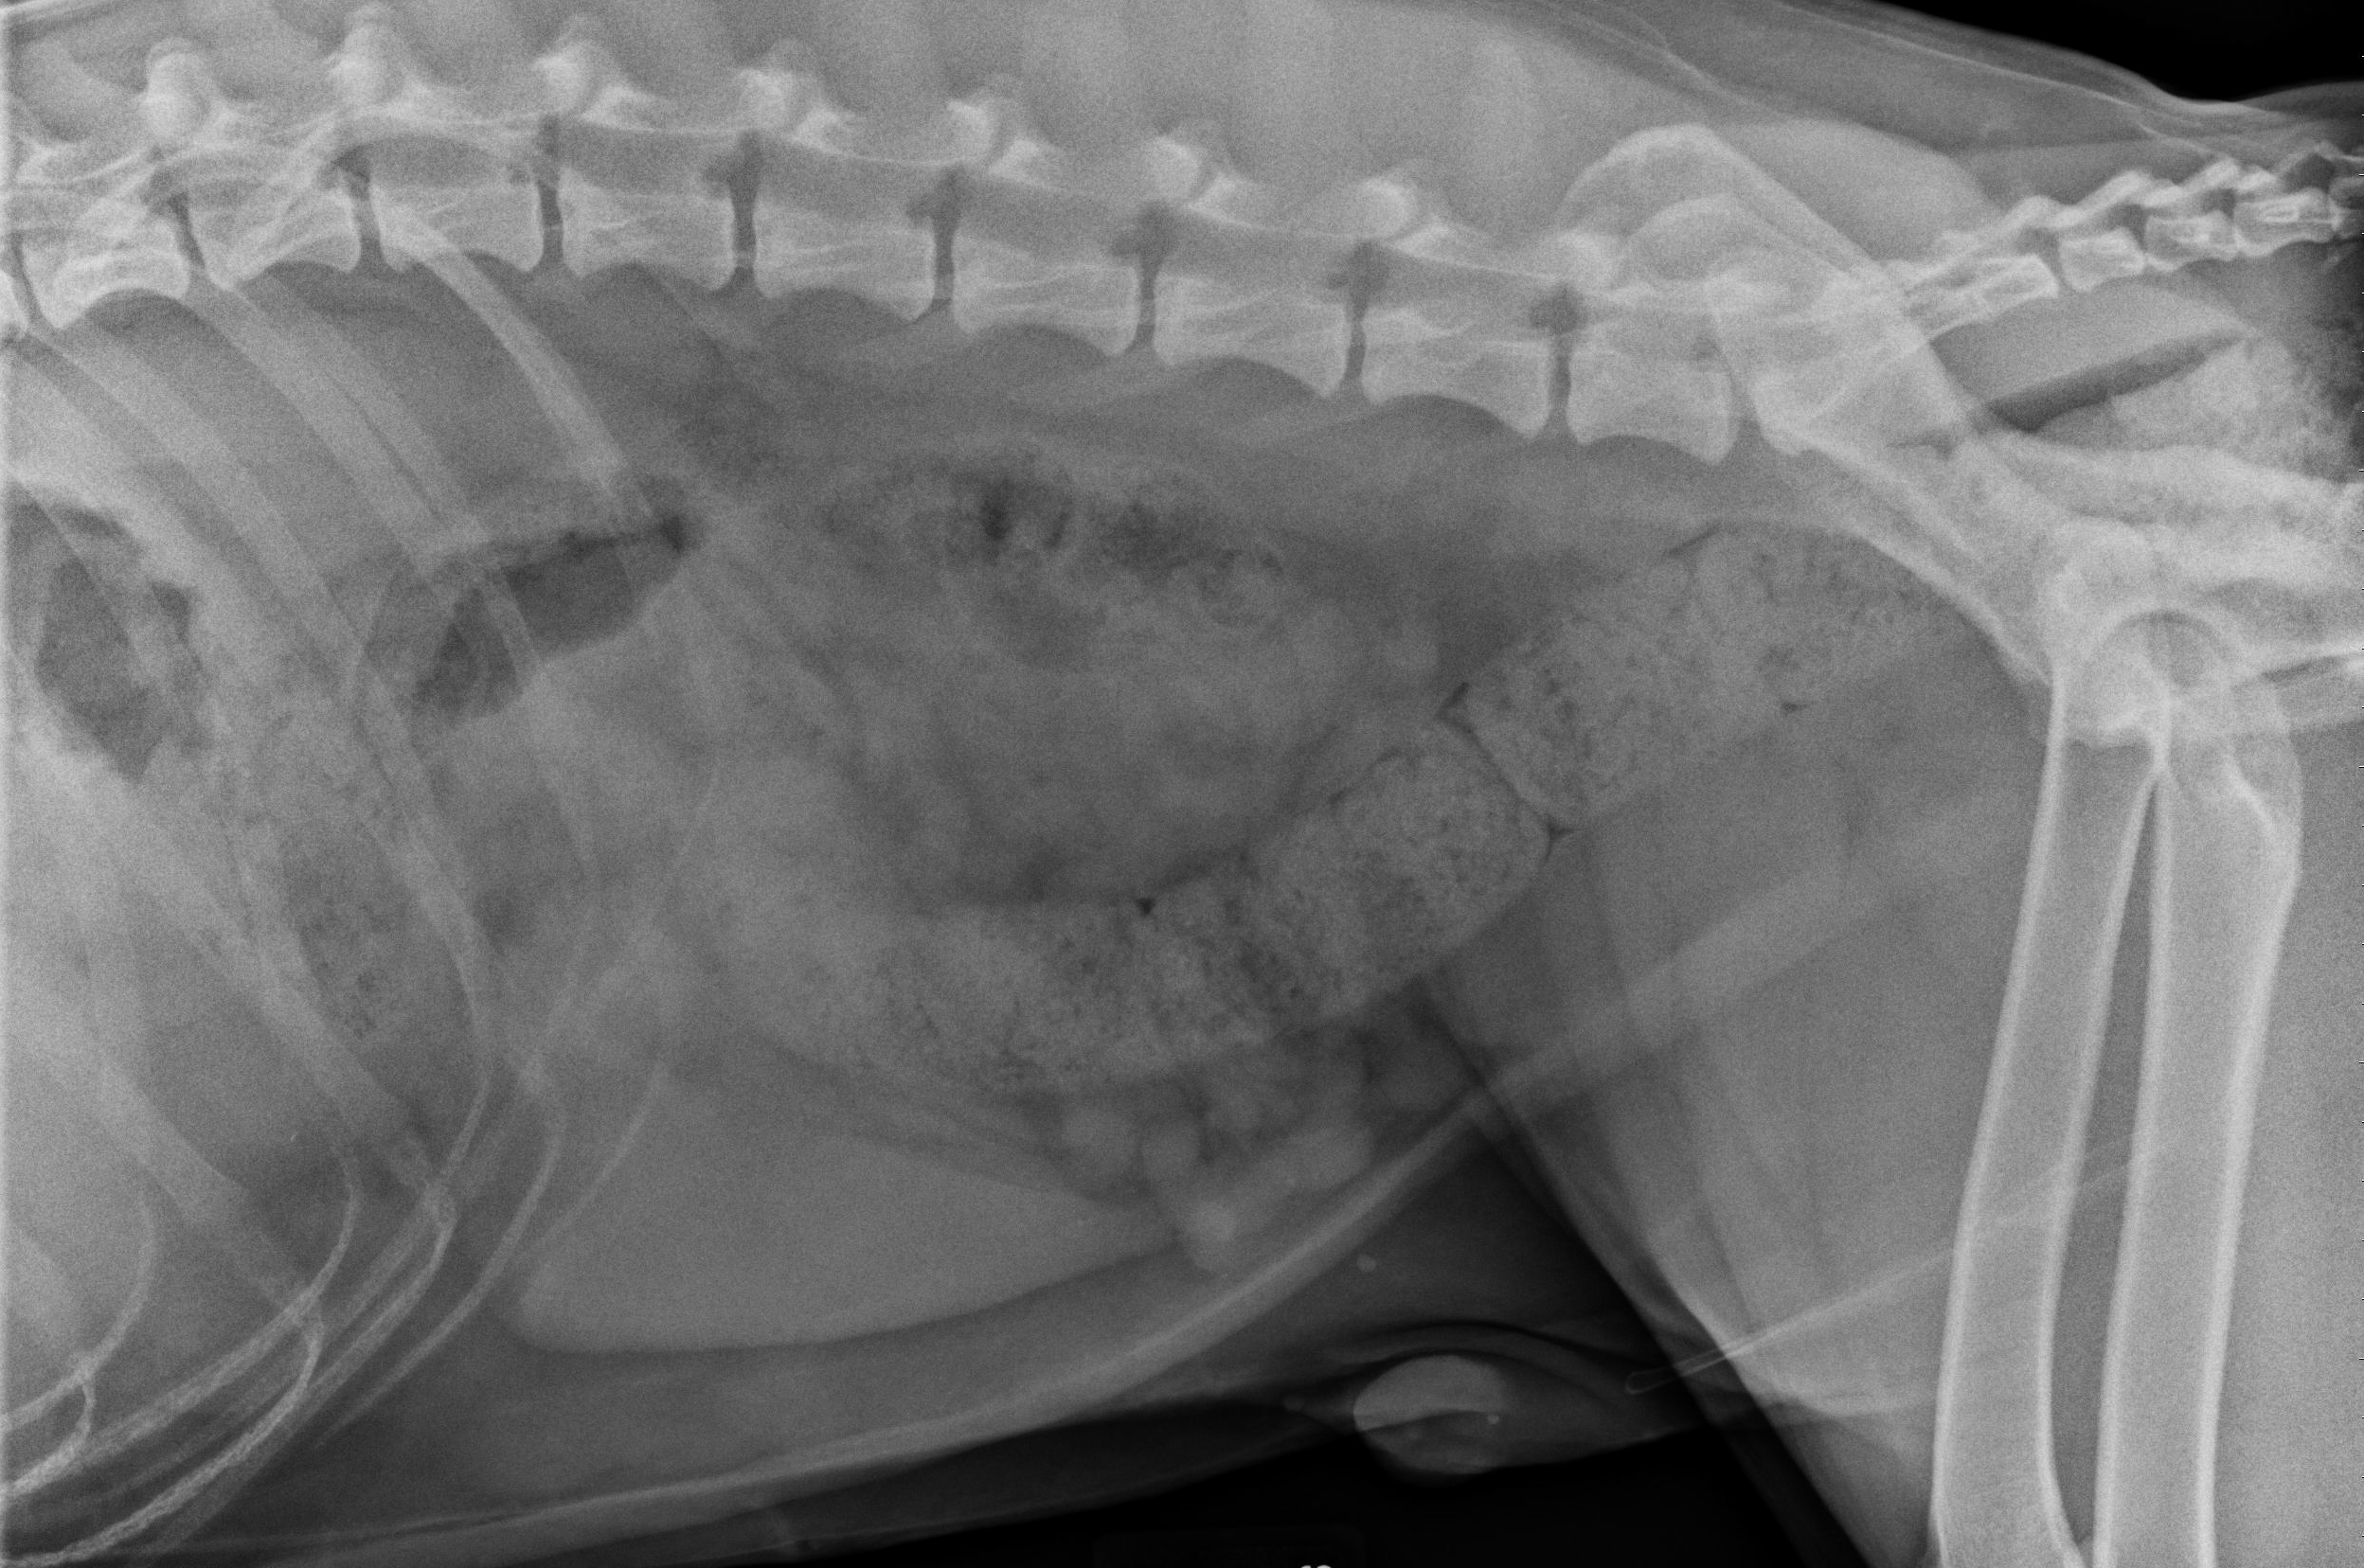

The video pretty much says it all! On dissection in between the 11th and 12th rib (deep to the rib) we found a stick that was lodged there and it was successfully removed. This was a very gratifying surgery. You may be asking, were was the stick – which is an excellent question, did it come from the abdomen, chest, etc? If there was direct communication within the abdomen, then we would be concerned with a septic (infection) peritonitis and likewise if it were within the chest cavity we would be concerned with a pyothorax (infection in the chest cavity). To help us determine this, another foley catheter was introduced (after copious flushing) into the space that was occupied by the stick and everything else was closed around the catheter. Contrast was injected into the catheter and a x-ray taken which showed the contrast in the stomach and not in the body cavity. Sequential x-rays were taken which showed the contrast in the gastrointestinal tract and not outside.